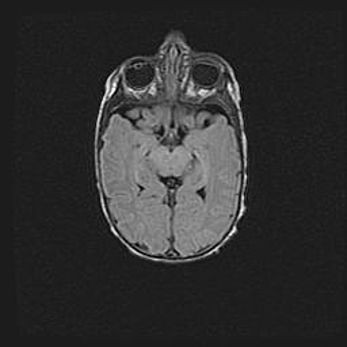

Неполная лизэнцефалия (пахигирия). Открытая гидроцефалия.

Возраст: 17 дней

Вес: 3110 г

Пол: мужской

Окружность головы: 33,5 см

Срок гестации: 35-36 недель

Лизэнцефалия—недоразвитие корковой пластинки и мозговых извилин в результате нарушения миграции нейронов коры. Поверхность мозговых полушарий гладкая. Микроскопически выявляется отсутствие нормальных слоев коры и скопление групп нейронов в подкорковом белом веществе.

Пахигирия—уменьшение числа вторичных извилин. В пораженном полушарии нервные клетки образуют толстый недифференцированный слой с неправильно расположенными нервными волокнами и группами гетеротопных клеток. Нервные клетки незрелые. Белое вещество истончено. При этом нередко аномально развит корково-спинномозговой путь.